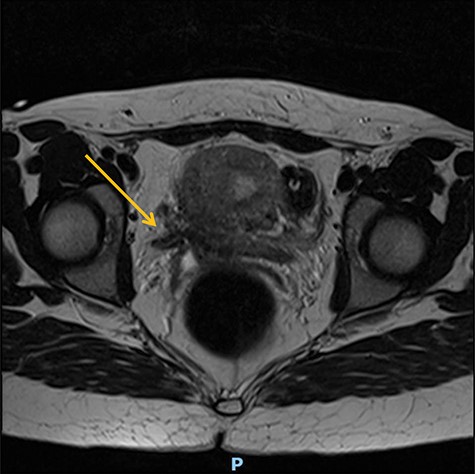

A 25-year-old woman was referred from a secondary hospital following a major uterine rupture at 40 + 6 gestation resulting in stillbirth and bladder injury. She was expected to deliver by vaginal birth after caesarean as she already had one child that was delivered by straightforward C-section. Labour was induced at 40 weeks due to high blood pressure, but during this process, the patient reported a tearing sensation in her lower abdomen and was taken to theatre for an emergency C-section and was discovered to have a uterine rupture and intrauterine foetal death. The C-section resulted in bladder injury and right ureteric transection. Subsequently, she developed a residual vesicovaginal fistula associated with ureteric obstruction at the level of the repair, and required nephrostomy and indwelling catheter drainage (Figures 1 and 2).

At a 1-year follow-up, the patient was complaining of flank pain, so an technetium-99m mercaptoacetyltriglycine renography (MAG3) was performed, showing good drainage but mild to moderate reflux into the reimplanted ureter. Normal bladder and sexual function were restored, and she was discharged from routine follow-up after 18 months. Following successful conception, she had a specialist obstetric review and was planned to have an elective C-section at between 37 and 38 weeks to avoid labour. Unfortunately, she had a premature vaginal delivery due to chorioamnionitis at 23 + 4 gestation complicated by sepsis with features of shock from which she and her baby made a full recovery (Figs. 1 and 2).

Preoperative MR abdomen, transverse plane. Arrow indicating obstructed right ureter